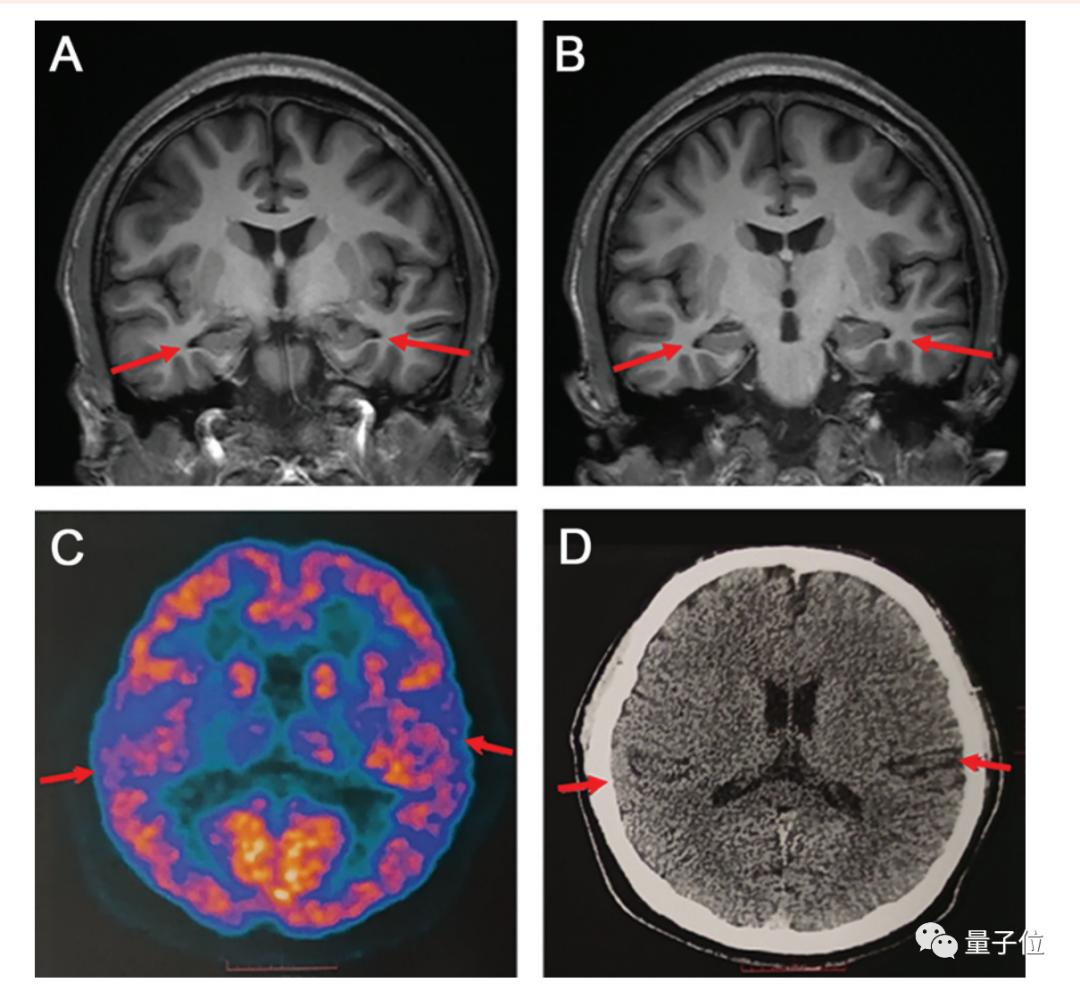

随后,医生们对男孩的大脑进行了核磁共振扫描,结果显示:其双侧海马体轻度萎缩,双侧颞叶也轻度萎缩,代谢水平低下。

要知道,海马体可是是人类大脑的重要结构,负责存储和加工记忆信息。

而颞叶则和语言、注意力、认知加工等功能都有关;颞叶萎缩,除了可能导致语言、注意力和记忆障碍;还可能导致情绪障碍、空间定向障碍等等。